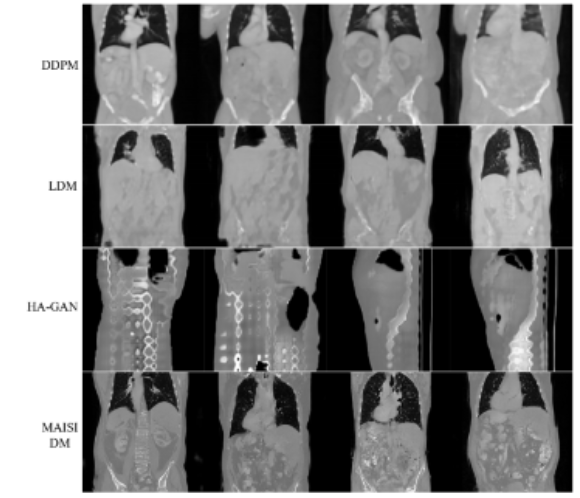

- 기존의 방법들(DDPM, LDM, HA-GAN)을 포함한 방법들과 비교하여 수행

- Fidelity(정확도)